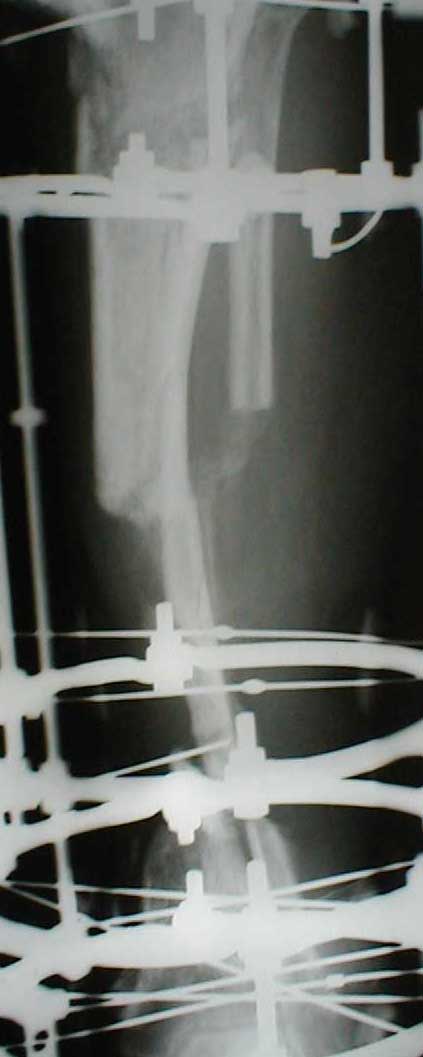

Dorogie kollegy,Have a nice day,Ja bi hotil obsuzdat' s Vami dvuh bolnih, kotorie postupili segodnjia ko mene. Pervy iz nih (OI) bolnoi s otkritoi tiazeloi mehanicheskoi travmoi Rt. leg segment v rezultate DTP, ot chego on imeet sledueshie povrezdenjia:- Otkrity perelom kostei pravoi goleny v srednei i niznoi ee trety s poteriem okolo 10 cm. kostnogo veshestva ot bolshebersovoi kosty, - Povrezdenjia a.tibialis post. s massivnim povrezdeniem zadneoi gruppy musculs goleny,- Malobersovjia kost' imeet segmentarny perelom, ee nizny fragment (kak Vi videte na foto) vistupaet na kozy okolo VNUTRENNOI Lodizky! - Traumaticheski Shock 2-3Drugih povrezdenjia net.

Nemedlenno bolnoi bil' intubirovan i provedeny vse protivoshokovie procedury, pravjia golen' bila pomeshenjia na apparat' Storm, dla reduksii kostei posle ee fiksasii k apparatu s pomoshio 2 spitsy 3mm D. Provedena Repozitsia pereloma i fiksirovana STORMOM vremenno, za tem sosudisty hirurg vypolnil 2 obhodnih anastomosa for a. Tibilis posterior, bili udaleny bolshie chasty iz musculov zadnoi gruppy goleny v predelah "vozmozno vedemih" zdorovoi tkany, oblast' pereloma promita by N. sol. 0.9% - 12 L. Zatem byla proizvedena okonchatenjia reduksia pereloma posle umerennoi traksii goleny na apparate, i fiksasiya pereloma s pomoshio apparata vneshnei fiksasii. Tak, Kakie soobrazanjia po dalneshemu vvdenjia bolnogo? On poluchaet antibiotiky i bolshie dozy LMH (Clexane 80 X 2) i vse ostalnoe......

Zdes' snimky posle poslednego montazha apparata prilagaiutsa

Yours Castro

Кликните для загрузки файла IMG_0501.jpg

13KB (14124 bytes)